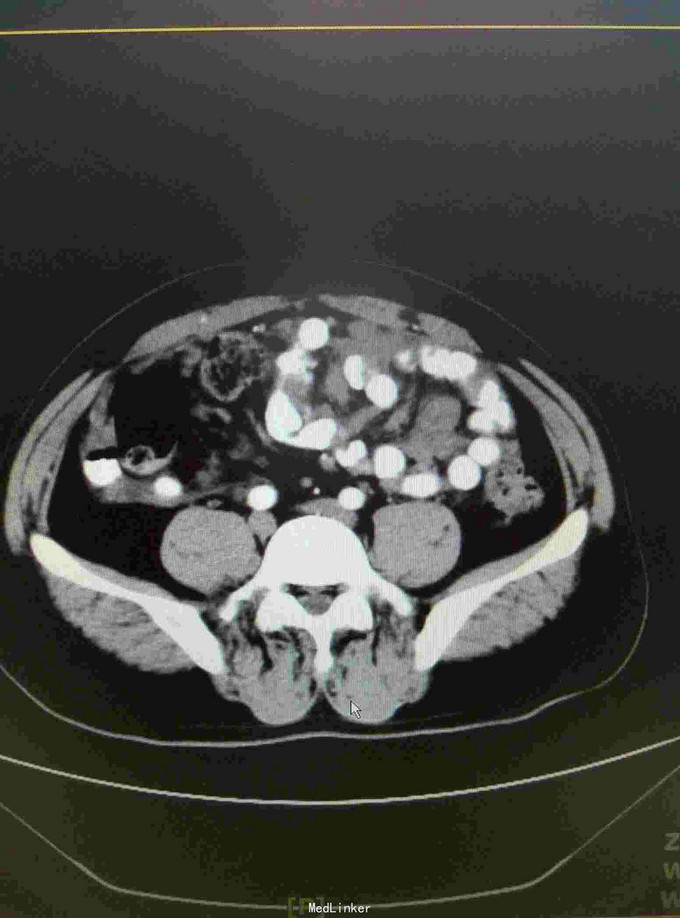

患者15年6月因腹胀就诊某医院行CT:疑似自发性腹膜炎,给予抗炎治疗。9月15日送检腹水发现增生间皮细胞。后去省影像中心行CT示:腹膜广泛增厚,强化,符合转移。后就诊我院腹膜肿物穿刺病理:促结缔组织增生性小园细胞瘤。后期贝伐单抗,IFO,THP,VCR,治疗。目前治疗中……